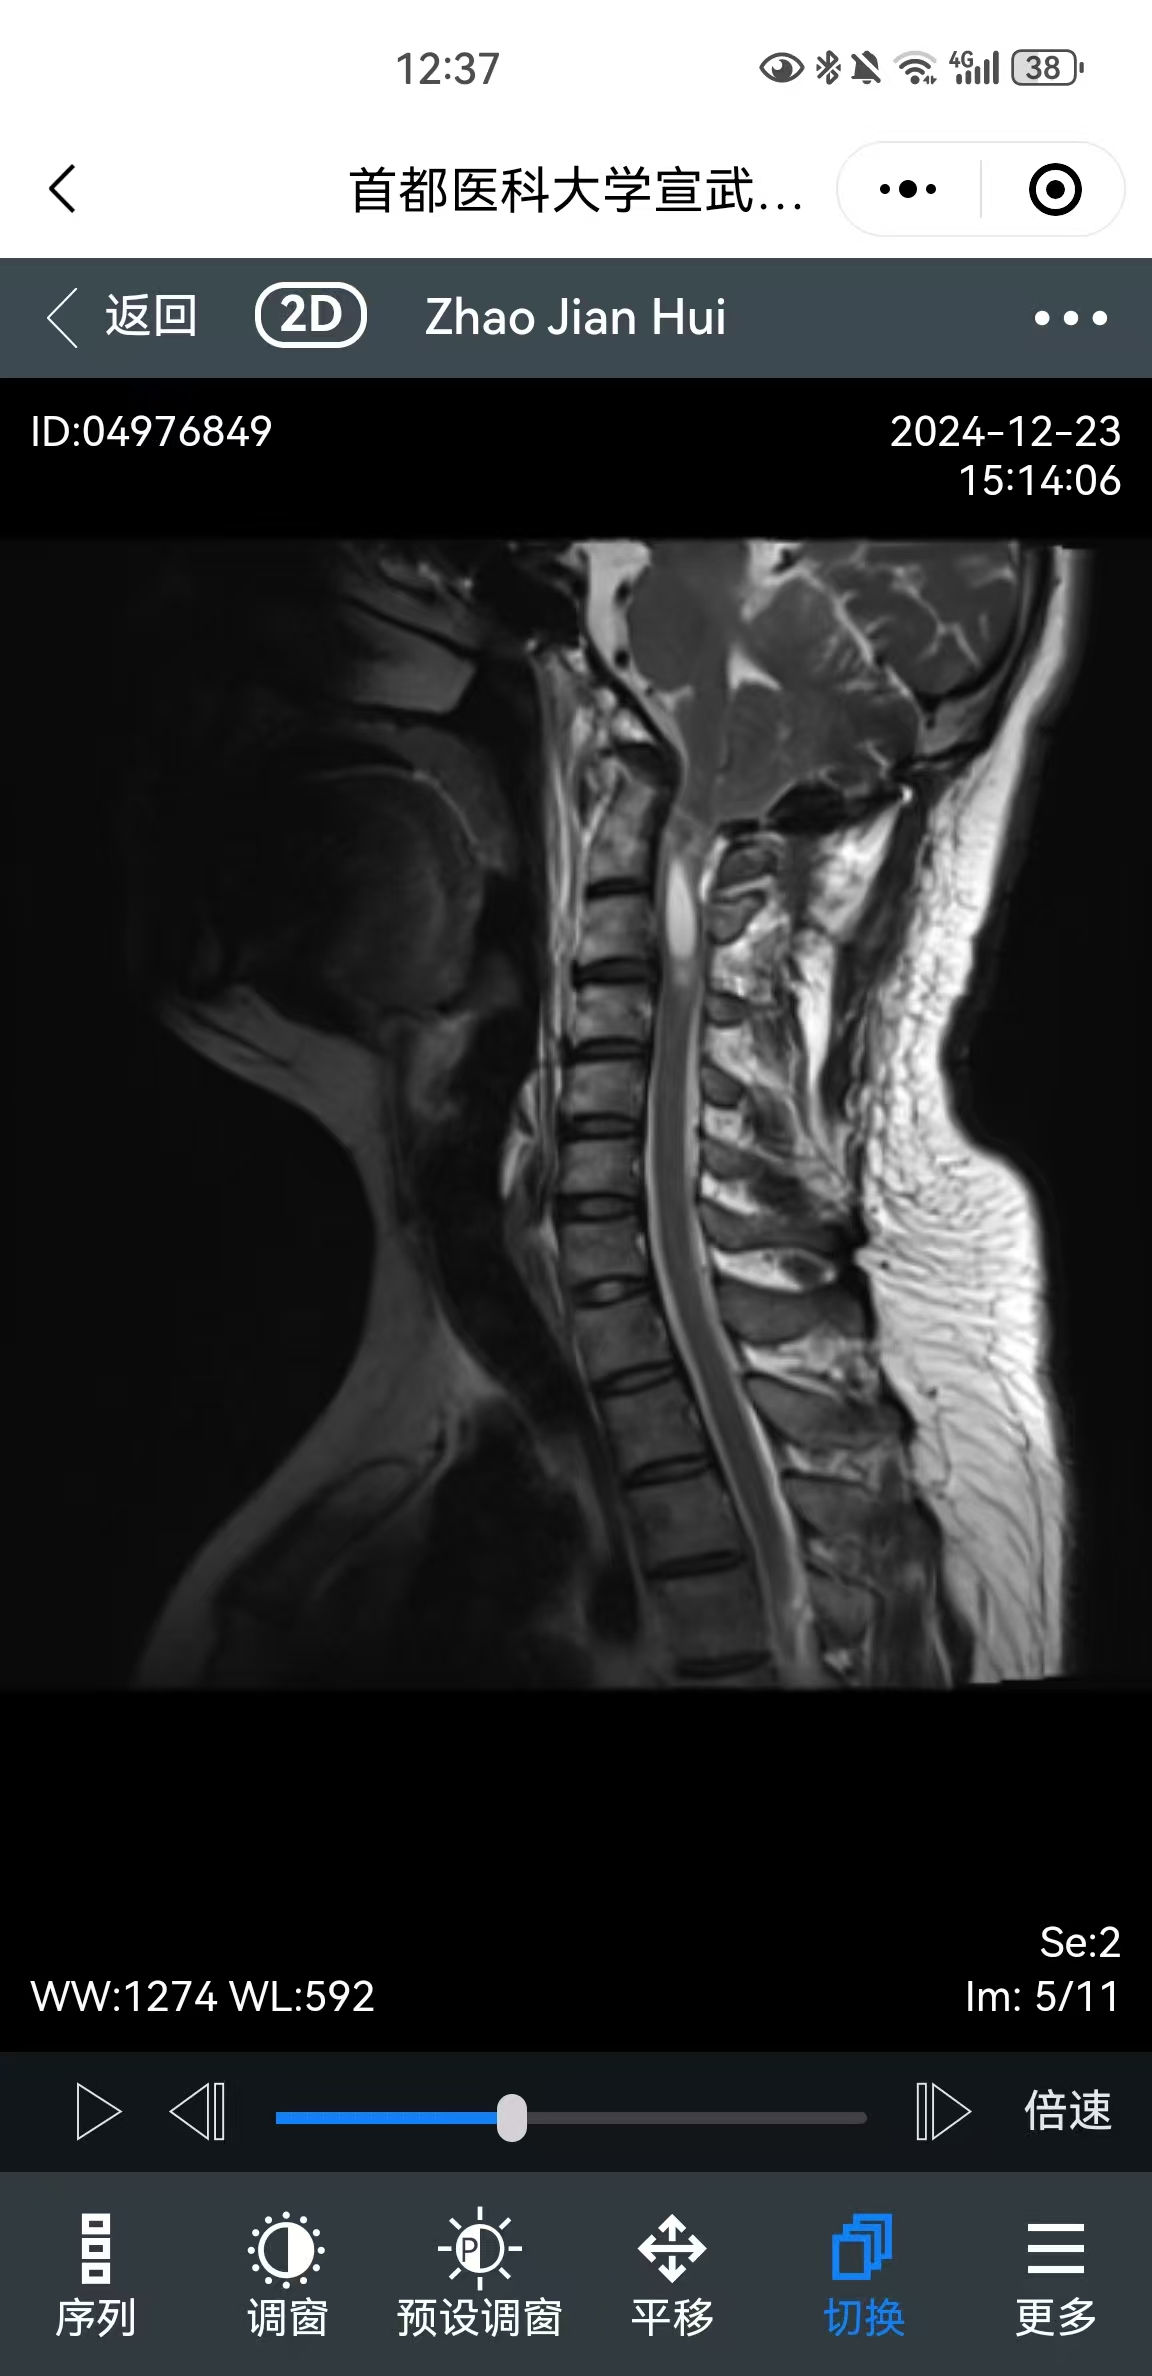

• 影像:

• 术后影像: